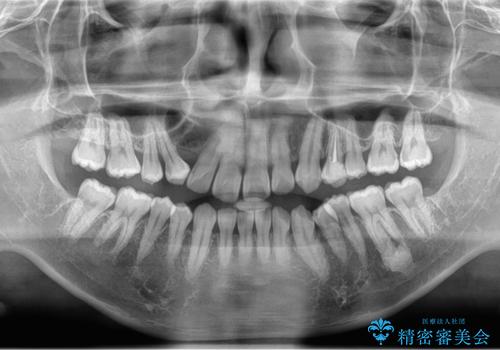

レントゲンを確認したところ上顎の犬歯が歯列不正により内側から生えてきたものでした。

抜歯をして欲しいとの依頼でしたのでCTを確認しながら抜歯術を行いました。